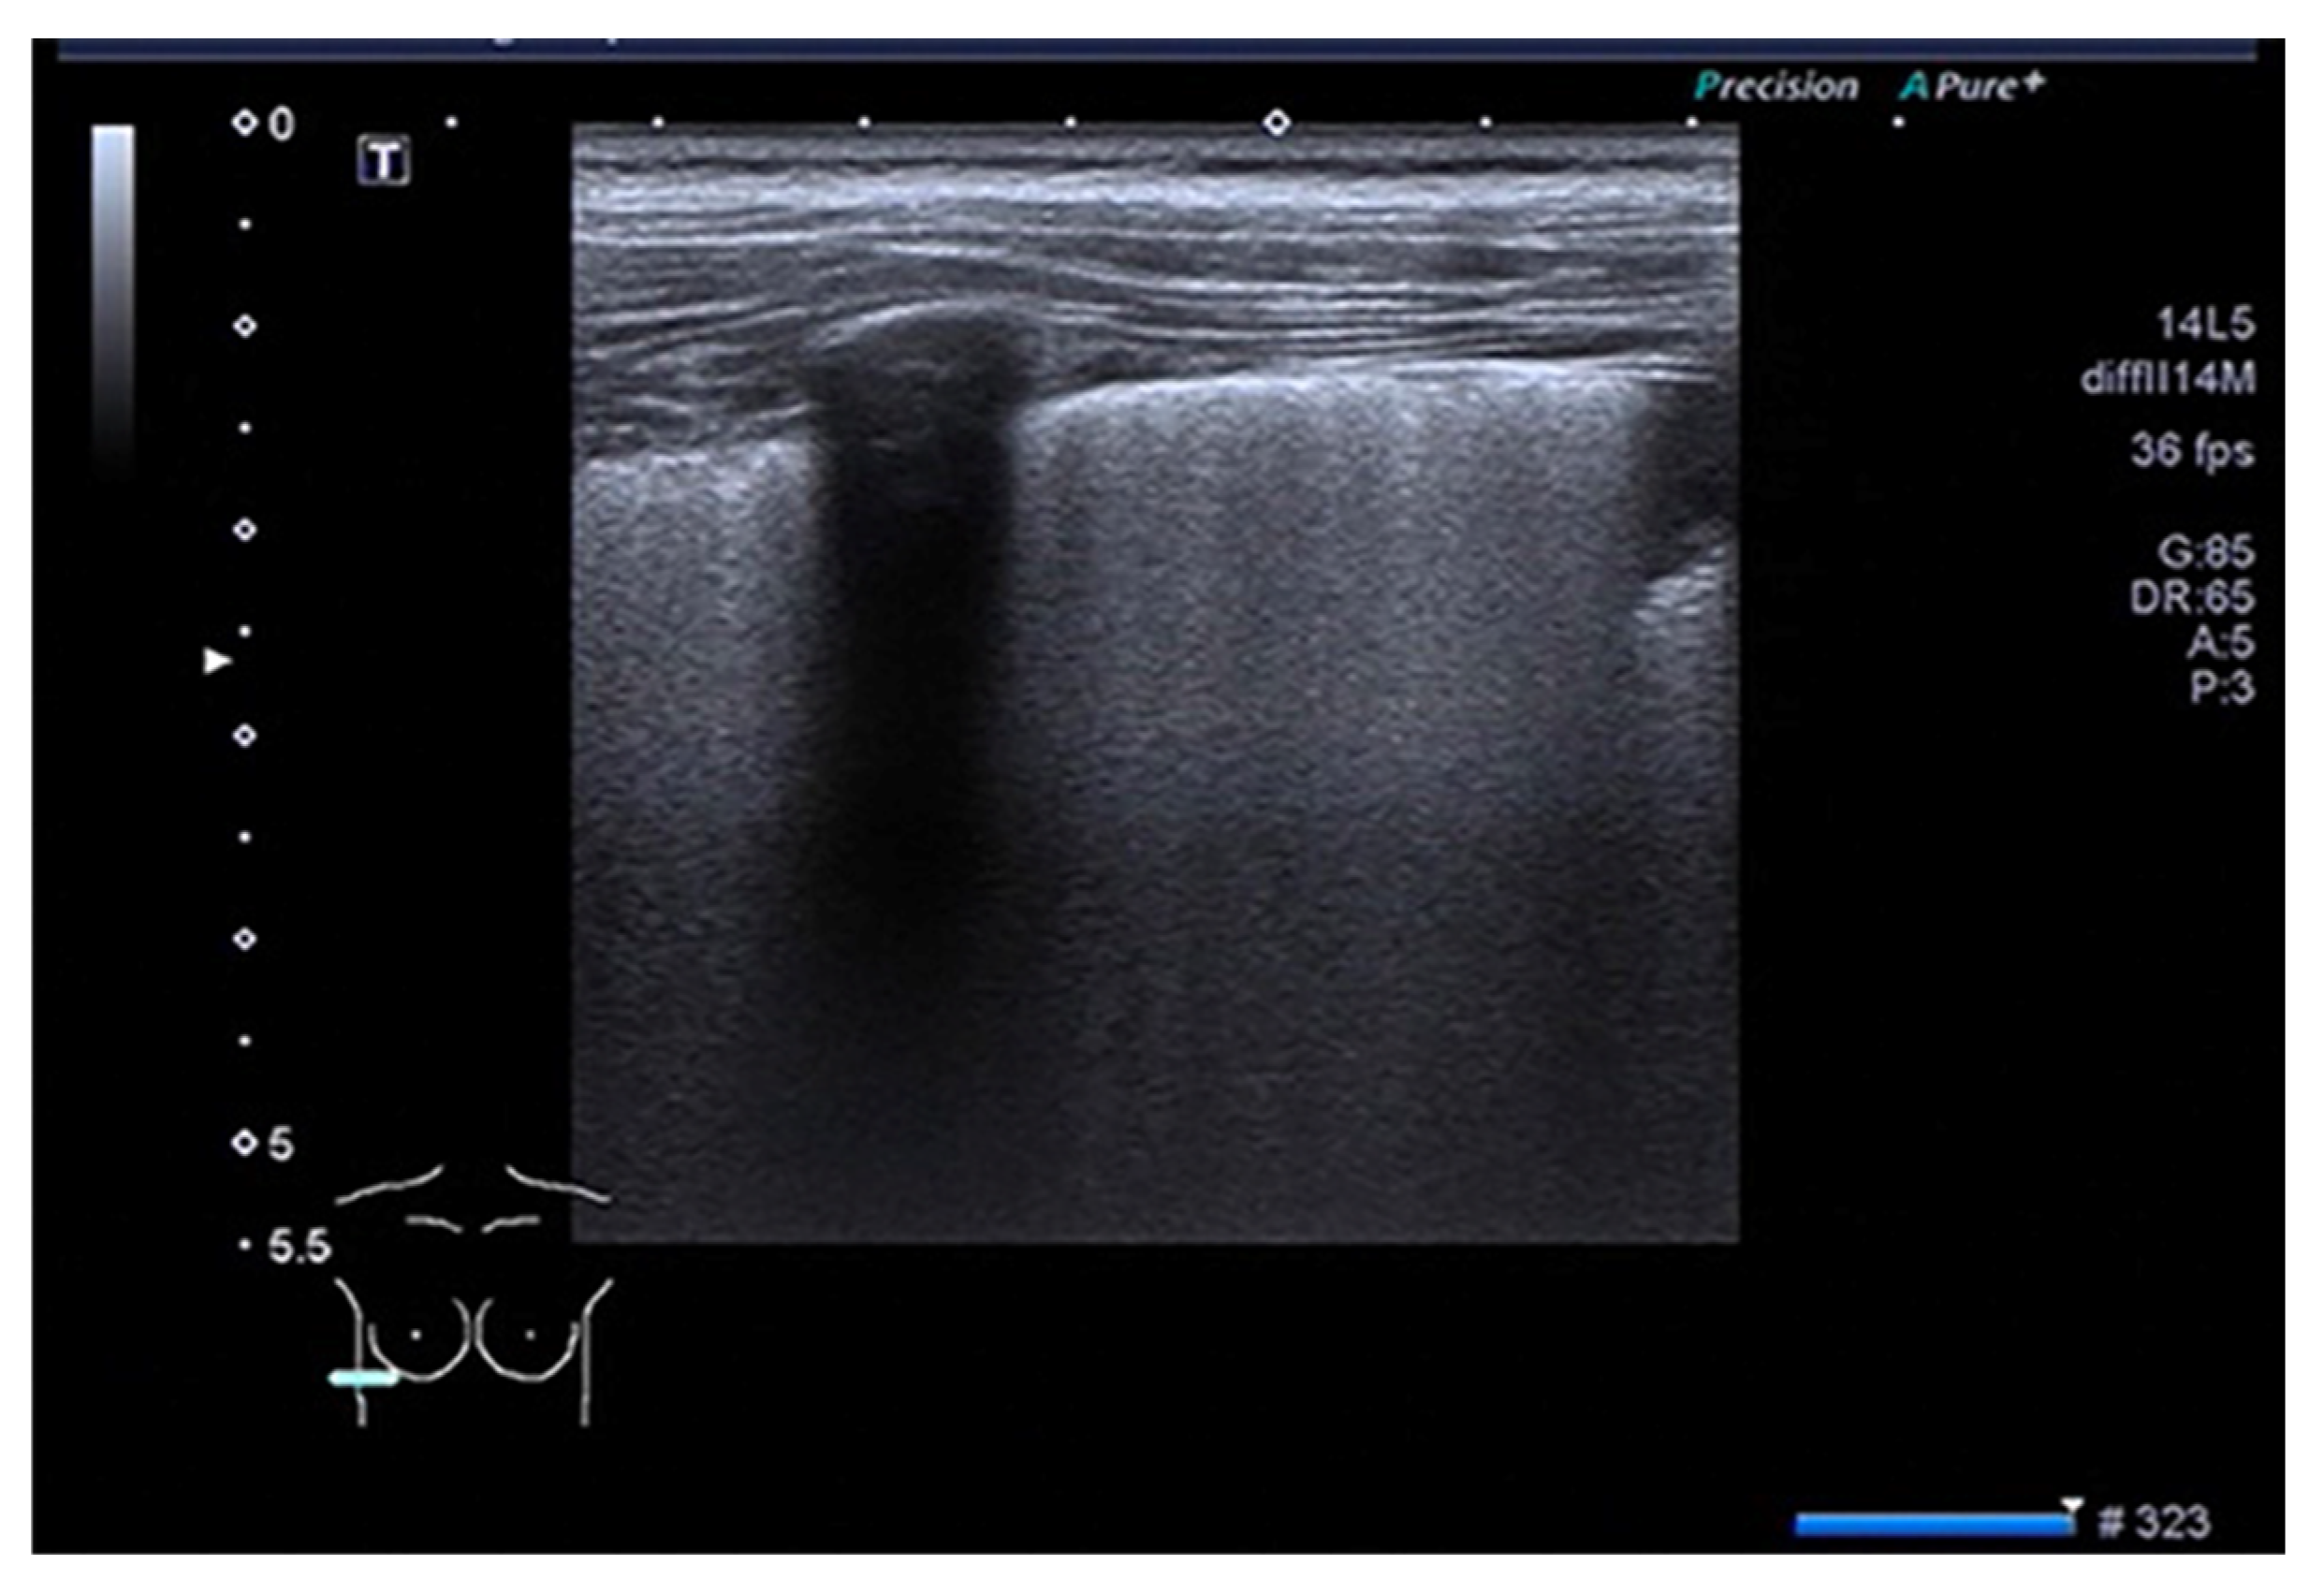

| Definition | |

|---|---|

| Consolidation | Area in which lung tissue is de-aerated with density similar to parenchymal tissues [23] |

| Atelectasis | Type of consolidation shown as hyperechogenic tissue structure visualized as solid parenchyma with static air bronchogram [11,24] |

| Cavitation | Solid, hypoechoic, heterogeneous lesions with sharp lobulated margins [11,25] |

| Pleural effusion | Hypo- or anechogenic structure, delineated by the chest wall and the diaphragm [11,26] |

| B-lines | Vertical reverberation artefacts from the pleural line to the edge of the scree; laserlike, vertical hyperechogenic artefacts synchronized with pleural line [11,23,27] |

| Pleural irregularities | Reduction or interruption of pleural line [11,28] |

| Sub-pleural nodes/granularities | Hyperechogenic subcentimetric granularities or consolidation under the pleural line [29,30] |